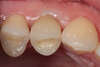

Radiographie post-opératoire d’un implant dentaire posé en lieu et place de la 1ère prémolaire maxillaire (photo 2). La couronne céramique est scellée sur le pilier. On peut observer une très bonne intégration autant esthétique que fonctionnelle, l’aspect est naturel et la patiente satisfaite.

Prémolaire maxillaire fracturée (photo 1) non conservable en l'état car le trait de fracture se situe sous le niveau de l'os de soutien. L'extraction est réalisée en urgence pour soulager la douleur et 2 mois plus tard un implant dentaire remplaçant la racine est posé. On attends ensuite 3 mois que l'implant s'intègre à l'os puis un pilier est transvissé sur l'implant (photo 2) et une couronne céramique est scellée sur ce pilier qui ne sera évidement plus visible (photo3).